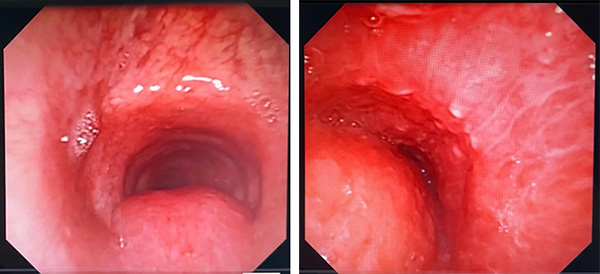

由于W先生病情危重,难以承受肌松麻醉,王洪武主任当机立断,敲定“软镜下Y形金属覆膜支架置入术”这一最优替代方案。随后,他亲自操作,团队成员全程协助,采用全麻下经口进软镜的方式开展操作,进镜后于中央气道Ⅰ区约声门下2cm处见膜部隆起致管腔狭窄约30%,中央气道Ⅱ区距隆突上5cm处外压型管腔狭窄约95%,病变长度约3cm,狭窄处气道几乎闭塞,这正是患者术前呼吸困难、无法平卧的核心原因。

支气管镜可见中央气道Ⅰ区狭窄30%;中央气道Ⅱ区狭窄95%